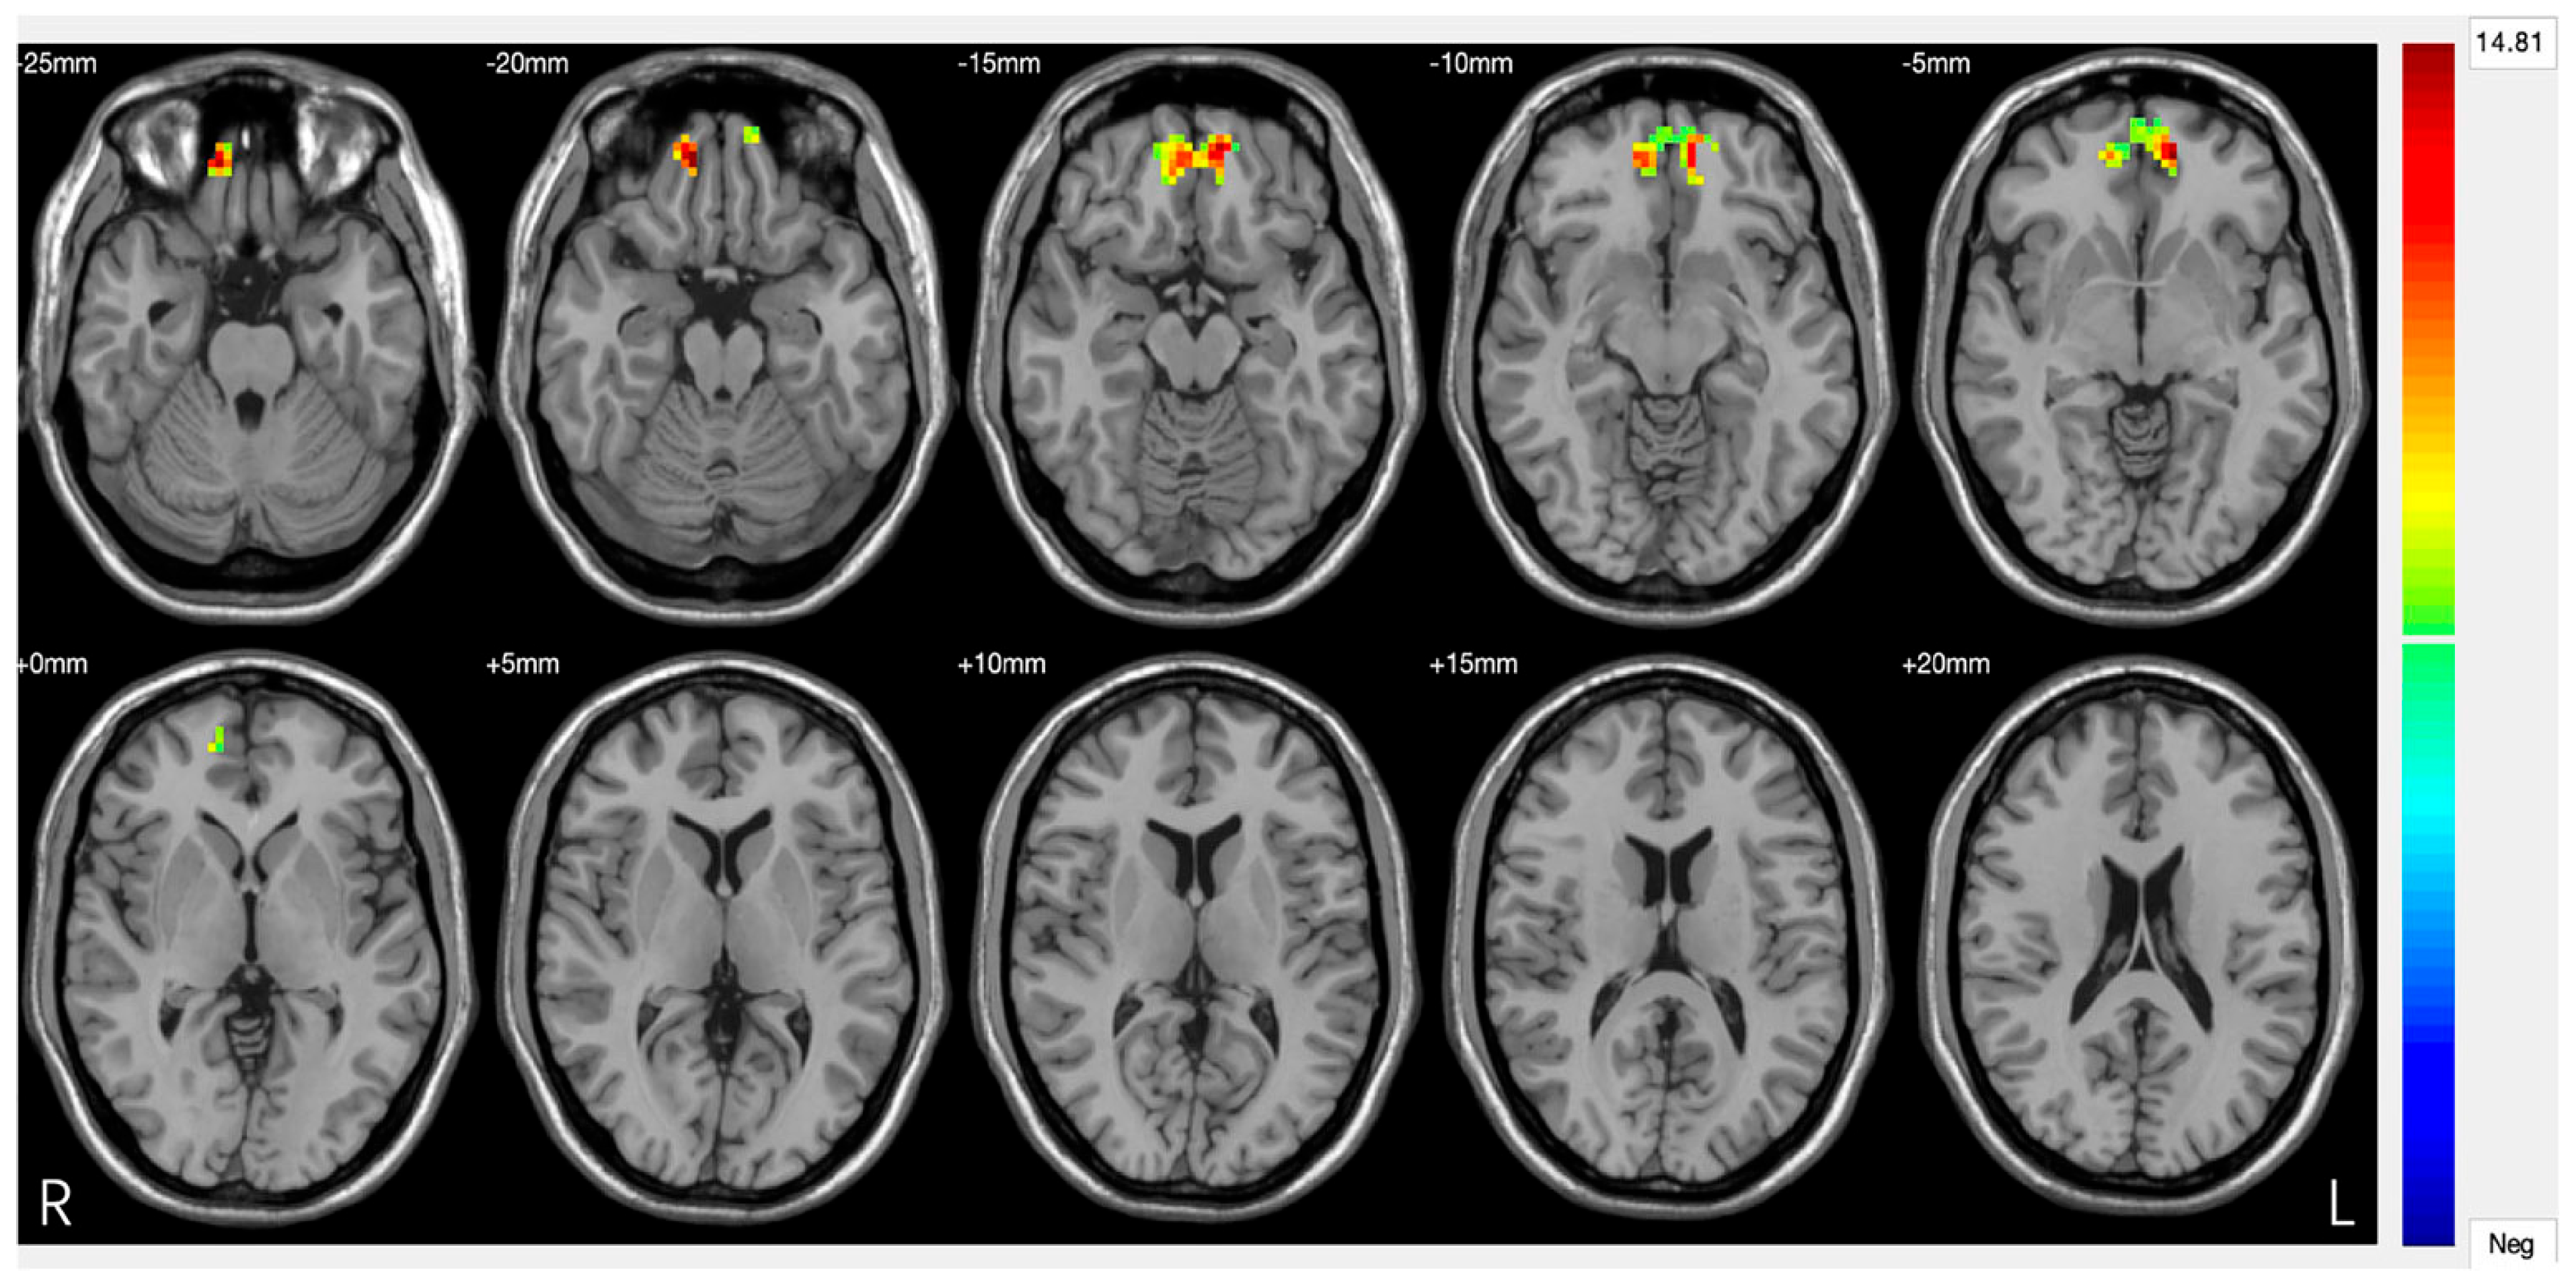

Prefrontal Cortex (DLPFC/VMPFC). The prefrontal cortex (PFC) represents the most consistently altered neural substrate in DS, with convergent evidence spanning over two decades of neurobiological research. The pattern of alterations specifically involves hypoactivation of the dorsolateral prefrontal cortex (DLPFC) and dysfunction of the ventromedial prefrontal cortex (VMPFC), creating functional compromises that correlate directly with depressive symptomatology. Meta-analytic evidence reveals widespread structural reductions in prefrontal regions in DS, with the left DLPFC showing 15–25% reductions in metabolic activity compared to healthy controls [53]. This hypoactivation becomes particularly evident during working memory, executive control, and cognitive emotion regulation tasks, manifesting through reduced cerebral perfusion and decreased glucose metabolism [54,55]. Functional magnetic resonance imaging studies have documented specific alterations in connectivity between the DLPFC and frontoparietal network, with 30–40% reductions in neural synchronization during complex cognitive tasks. These dysfunctions correlate significantly with neuropsychological assessments of executive functions, sustained attention, and working memory, providing a neurobiological foundation for the cognitive symptoms commonly observed in DS [56]. The VMPFC presents complementary alterations, characterized by anomalous hyperactivation during negative emotional stimulus processing and hypoactivation during voluntary emotional regulation tasks [57]. This pattern reflects a 35–50% compromise in top-down modulation effectiveness of limbic structures (Figure 2), determining reduced cognitive control over emotional responses [58]. The therapeutic implications of prefrontal dysfunction have been particularly well-demonstrated through repetitive transcranial magnetic stimulation (rTMS) research. High-frequency stimulation of the left DLPFC has shown robust antidepressant effects, with accelerated protocols achieving 60–75% remission rates in treatment-resistant patients [59]. The identification of specific connectivity profiles between stimulation sites and the subgenual anterior cingulate cortex has further refined targeting strategies, demonstrating how understanding neural correlates can directly inform therapeutic approaches [60].

Figure 2.

Major depressive disorder: new clinical, neurobiological, and treatment perspectives [61].